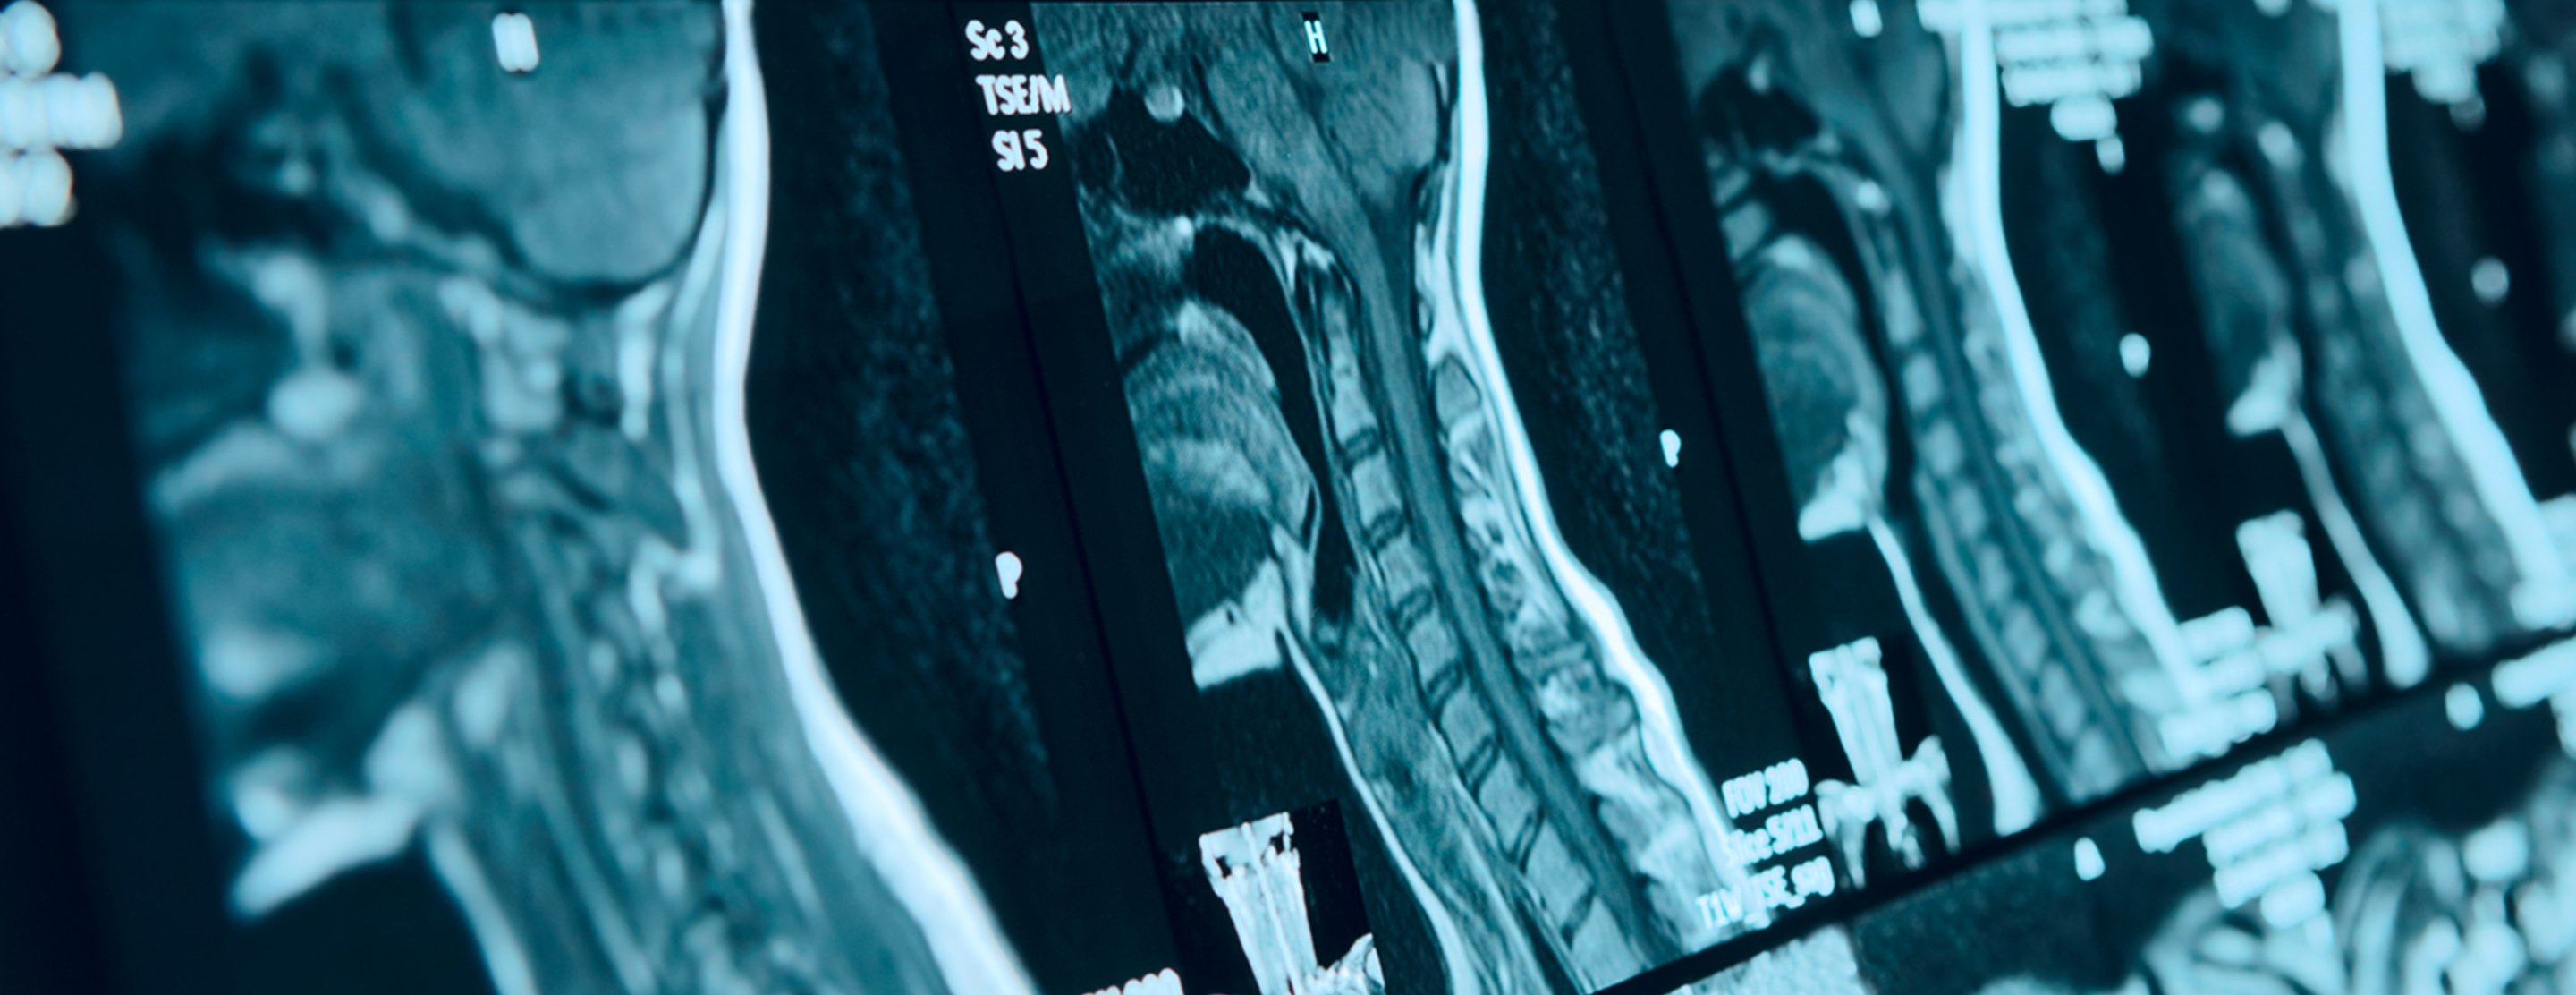

Cervical MRI scan

A cervical MRI (magnetic resonance imaging) scan uses energy from strong magnets to create pictures of the part of the spine that runs through the neck area (cervical spine).